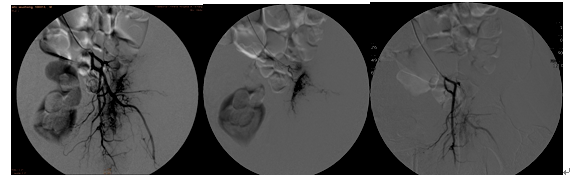

患者、男、53岁,前列腺癌左髋关节转移剧烈搏动性疼痛,关节不能伸直,行左侧转移瘤相关血管栓塞术后患者疼痛消除。